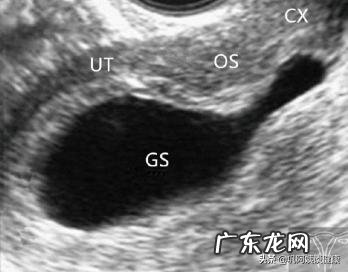

病例一(见图1)

患者女,39岁 。主诉:停经62天,阴道少量出血1天伴腹痛 。病史:G3P0,人工流产1次,自然流产1次,尿妊娠阳性 。

妇科检查:子宫孕5周大小,阴道内少量暗红色血液,宫颈外口略开 。

超声检查:子宫偏大,子宫内口扩张,宫腔底部至颈管内见呈水滴状妊娠囊结构,未见卵黄囊及胚芽 。

超声提示:宫内妊娠囊变形,未见胚芽(难免流产可能) 。

人工流产后病理:绒毛水泡状变性 。